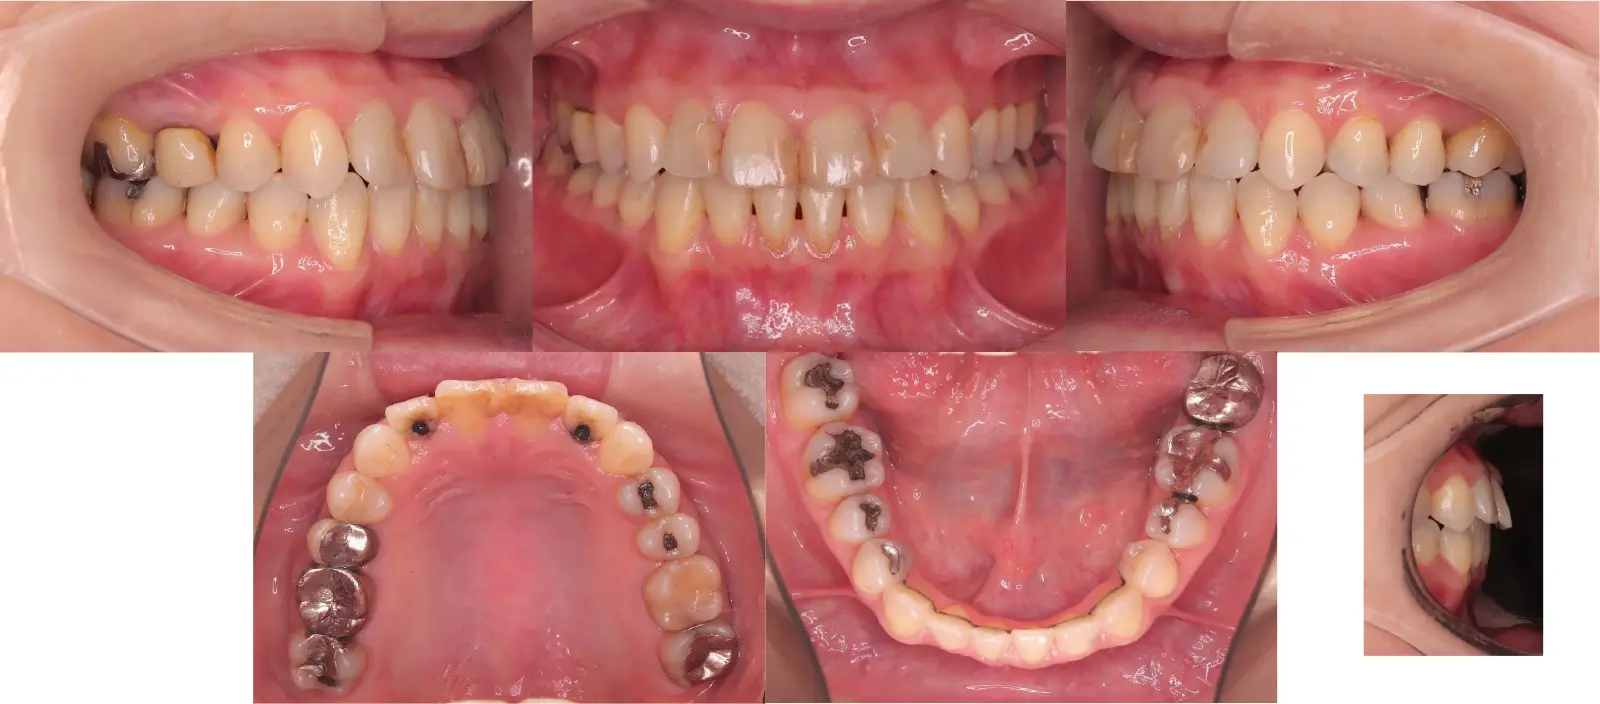

軽度叢生を伴う切端咬合

- 主訴

前歯で噛めない

- 年齢

47歳

- 治療期間

2年5ヶ月

- 治療回数

20回

- 治療に用いた主な装置

カスタムメイドリンガル矯正装置(WIN)

- 治療費

1,200,000円(税別)トータル料金

- 抜歯部位

上顎左第二大臼歯1本 下顎左第三大臼歯1本